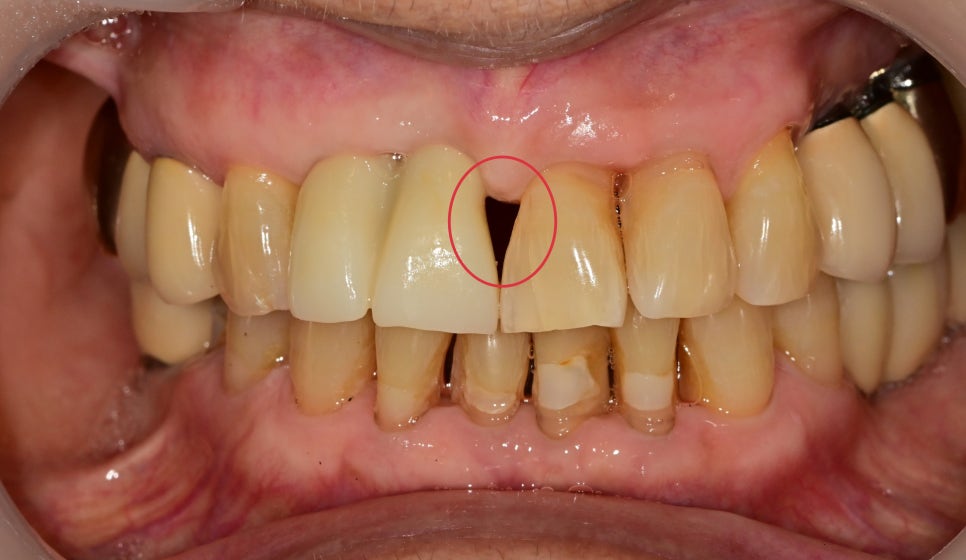

앞니 2개 부분에서 잇몸도 붓고 피가 자주 난다고 내원해 주셨습니다

치열이 틀어져 있고, 치아가 너무 붙어있어 그로 인한 치주의 구조 자체가

치주 질환이 생길 수밖에 없는 구조였습니다

임플란트가 안정이 되고 임시치아를 시적 한 사진입니다.

처음 내원하셨을때 사진과 비교해 보면

흔들렸던 치아가 틀어져있고, 주변 잇몸이 부어있는 상태에서

임플란트 보철로 치열이 가지런해지고 잇몸이 가라앉은 상태로 되었고

대칭되는 옆 치아와 치아 형태를 똑같이 만들다 보니 잇몸 사이 공간이 더 커보였습니다.